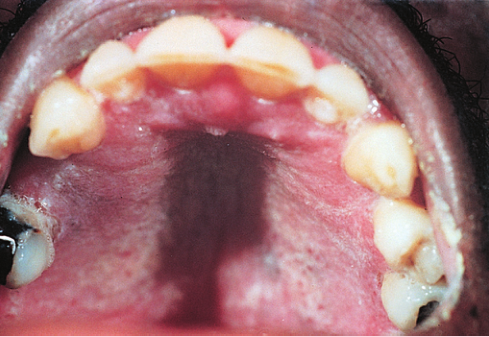

BOX 16.4口腔念珠菌病

43岁,女性,出现口腔酸痛和吞咽困难,两周,未服用任何药物,未孕,余无不适。医生诊断其为念珠菌感染(Fig16.11),病人服用抗真菌药物后,效果很好。然而,假丝酵母在两周后又回来了。这就让医生不得不思考一个问题,那就是病人为什么会患上复发性念珠菌病。

念珠菌是所有年龄段、性别的共同问题。例如,许多服用抗生素的人会患上念珠菌,在口腔中生存的常见细菌被消灭了,而念珠菌就可以接管。念珠菌也经常出现在服用皮质类固醇(作为片剂或吸入剂)治疗哮喘的人中。皮质类固醇对抗原提呈细胞和T细胞都有广泛的影响。细胞毒性化疗药物也经常引起念珠菌。这些药物会导致中性粒细胞减少,因此防御念珠菌的细胞减少。然而,我们的病人没有服用这些常见的药物。

复发念珠菌的另一个非常罕见的原因是自身免疫性多内分泌病假丝酵母菌病外胚层发育不良综合征(Box15.2),但我们的患者没有这种特征。在APECED中,患者产生针对IL-17的自身抗体,这会阻止辅助性T17(TH17)细胞的正常功能。

复发念珠菌可能是HIV感染早期的一个特征,因为这会导致CD4+T细胞的丢失,包括TH17细胞。他做了HIV抗体检测,结果呈阳性。于是患者开始接受抗逆转录病毒治疗,效果非常好。

Fig 16.11 这名男子腭部的白色病变是口腔念珠菌病,这是轻度免疫缺陷的标志。它通常是HIV患者出现的第一个机会性感染。口腔念珠菌病也常见于其他轻度继发性免疫缺陷。(由英国伦敦圣巴塞洛缪医院提供。)